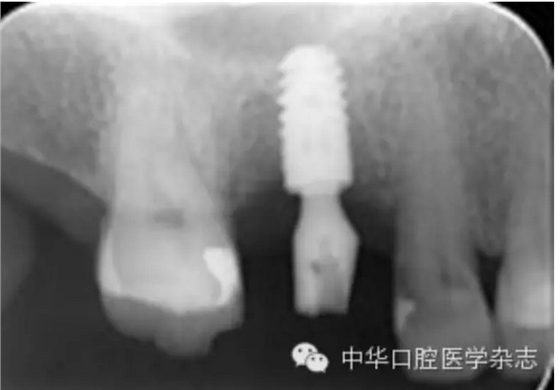

【摘要】目的 分析平臺轉(zhuǎn)換種植修復(fù)基臺折斷原因,探討處理辦法及預(yù)防策略。方法 2001年1月至2014年12月植入的平臺轉(zhuǎn)換種植體2 487枚中,2009年3月至2014年2月發(fā)生平臺轉(zhuǎn)換種植修復(fù)基臺折斷6例,男性5例、女性1例,平均年齡63歲(55~78歲),均使用Ankylos®種植系統(tǒng),6例均為修復(fù)完成2~8年后發(fā)生修復(fù)基臺折斷。分析修復(fù)基臺折斷與力及其連接方式等因素的關(guān)系。結(jié)果基臺折斷率為0.24%(6/2 487)。6例折斷基臺均發(fā)生在磨牙區(qū)、牙冠面均為貴金屬。6例折斷基臺均無法完整取出,最終取出種植體后重新種植修復(fù)。結(jié)論 平臺轉(zhuǎn)換種植修復(fù)基臺折斷后取出困難,應(yīng)注重預(yù)防此嚴(yán)重并發(fā)癥。磨牙區(qū)種植修復(fù)應(yīng)謹(jǐn)慎使用平臺轉(zhuǎn)換種植系統(tǒng);通過增加種植體數(shù)量、采取烤瓷聯(lián)冠修復(fù)可能降低基臺折斷風(fēng)險。使用小直徑、短種植體可減少取出種植體時的創(chuàng)傷,有利于再次種植。